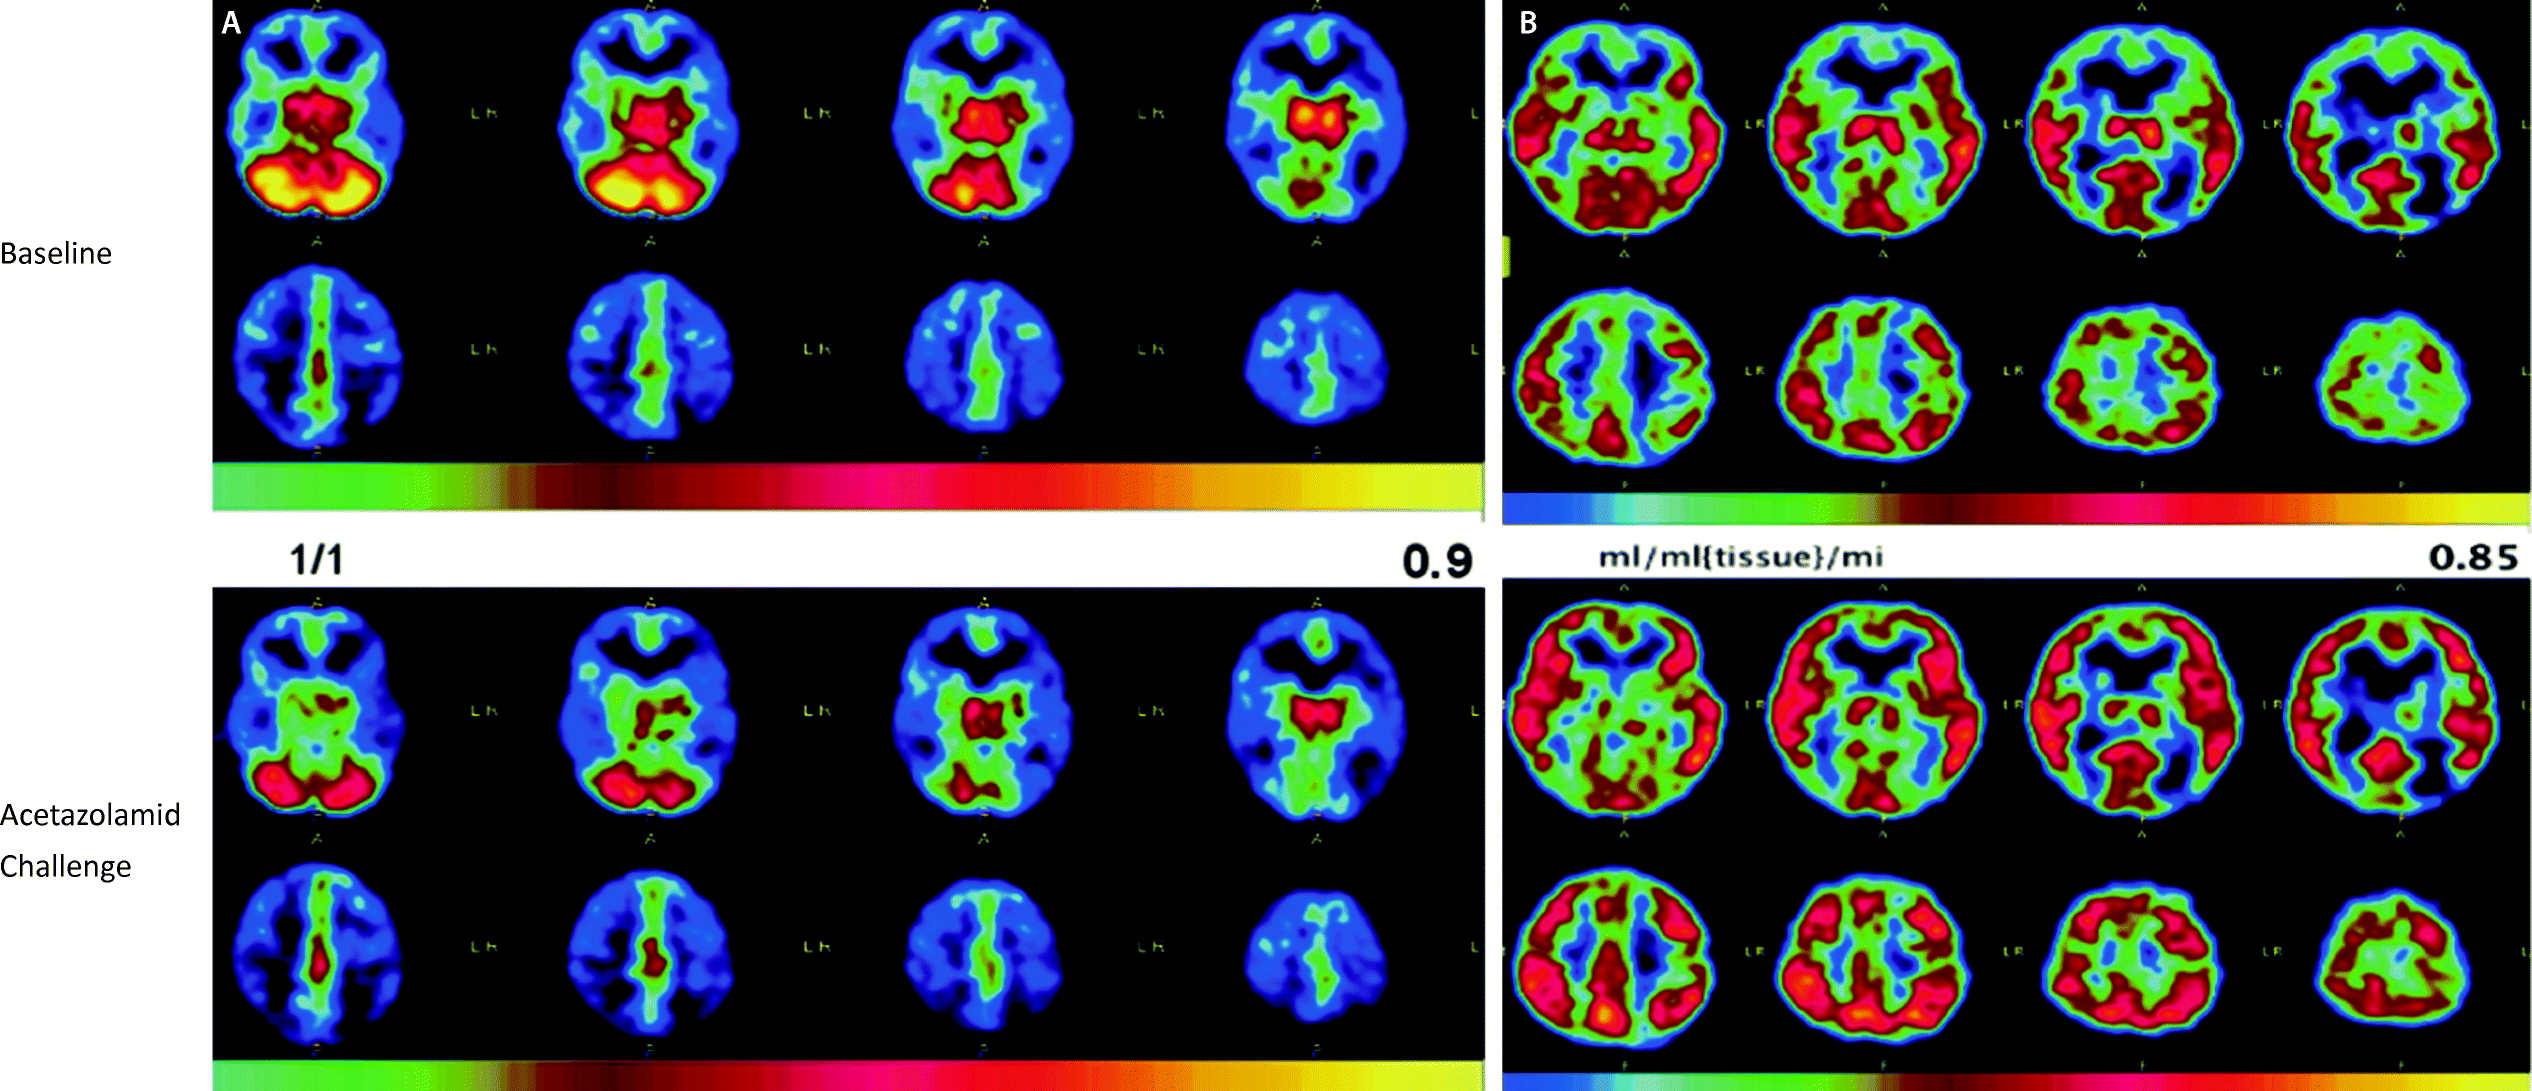

Abb 4 8 Moyamoya Erkrankung Download Scientific Diagram

Diagnostik Und Therapie Der Moyamoya Erkrankung